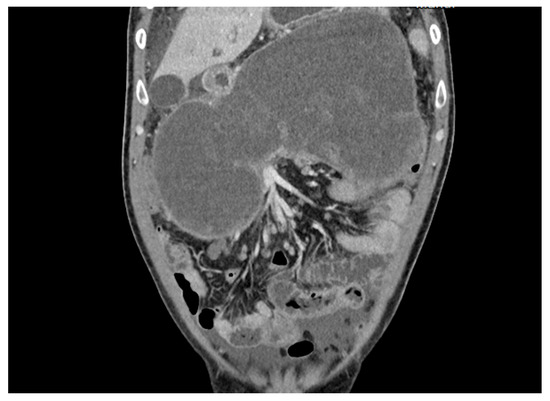

2. Detailed Case Description

2.2. Results